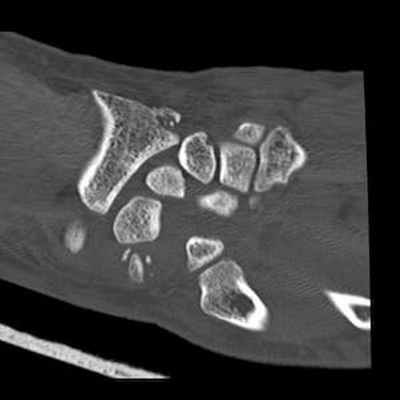

Трансладьевидно-перилунарный вывих запястья III-его типа

Трансладьевидно-перилунарный вывих запястья (перелом ладьевидной кости в виде основной сагиттальной линии, с образованием двух сильно смещенных фрагментов; проксимальный фрагмент остается в нормальном соотношении с полулунной костью; разъединение костей первого и второго ряда запястья).

Наличие мелких костных фрагментов вокруг трехгранной кости вместе с отрывными переломами; смещение кзади трехгранной кости.

Оскольчатый перелом шиловидного отростка лучевой кости.

Локтевая кость цела.